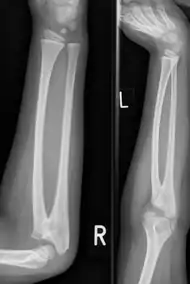

Radioulnar synostosis is a rare condition where there is an abnormal connection between the radius and ulna bones of the forearm.[1] This can be present at birth (congenital), when it is a result of a failure of the bones to form separately, or following an injury (post-traumatic).[2]

| Congenital radioulnar synostosis in a 7 year old boy | |

It typically causes restricted movement of the forearm, in particular rotation (pronation and supination), though is not usually painful unless it causes subluxation of the radial head.[1] It can be associated with dislocation of the radial head which leads to limited elbow extension.[2]